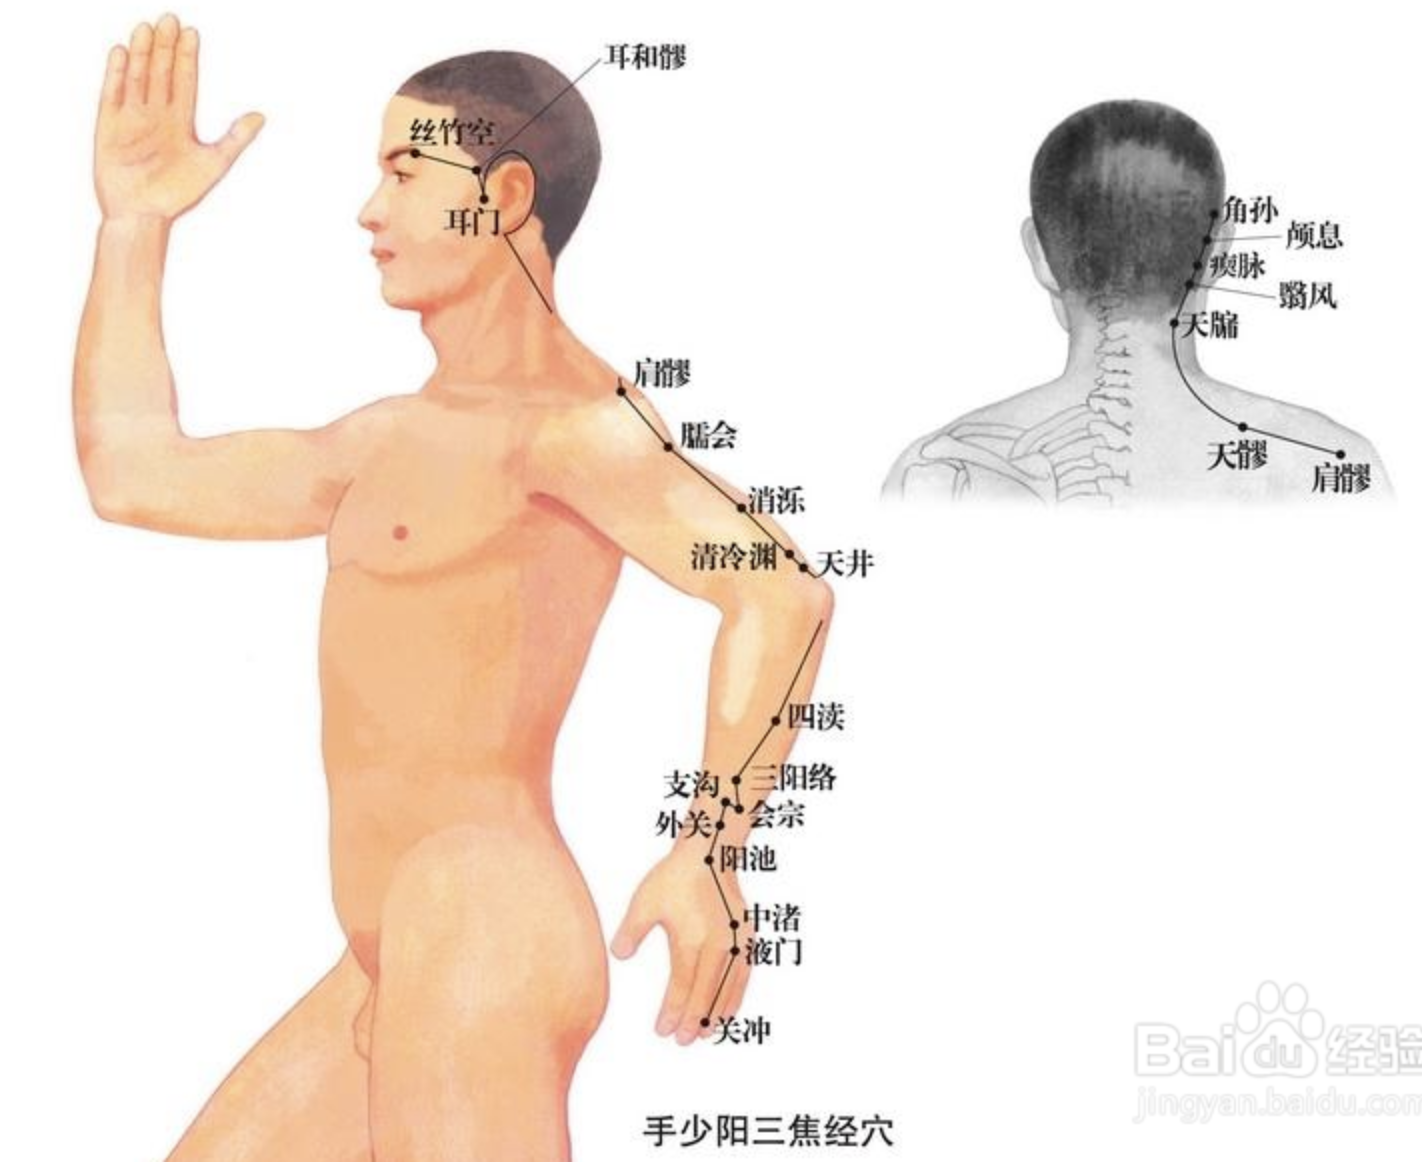

【(十)手少阳三焦经(图10-28)】

1、时辰 亥时 21 ~ 23

2、歌诀 二十三穴手少阳,关冲液门中渚旁。阳池外关支沟正,会宗三阳四渎长。天井清冷渊消泺(luò),臑会肩髎天髎堂。天牖(yǒu)翳风瘛(chì)脉青,颅息角孙丝竹空。和髎耳门听有常。

3、经脉循行 起于无名指末端(关冲)上行于第 4、5掌骨间,沿腕背、出于前臂外侧尺桡骨之间,经肘尖沿上臂外侧达肩部,交大椎,再向前入缺盆部,分布于胸中,络心包,过膈,从胸至腹,属于上、中、下三焦。

胸中支脉:从胸向上出于缺盆部,上走项部,沿耳后直上至额角,再下行经面颊部至目眶下。

耳部支脉:从耳后入耳中,出耳前,与前脉交叉于面颊部,到目外眦,与足少阳胆经相接。

4、主要病候 腹胀、水肿、遗尿、小便不利、耳聋、咽喉肿痛、目赤肿痛、颊肿、耳后、肩臂肘外侧痛等。

5、主治概要 主治侧头、耳、目、胸胁、咽喉病、热病及经脉循行部位的其他病证。

关冲

【定位】 在手无名指末节尺侧,距指甲角 0.1 寸(指寸)。

【主治】 头痛,目赤,耳聋,耳鸣,喉痹,舌强,热病,心烦。

【配伍】 配内关、人中治中暑、昏厥。

【刺灸法】 浅刺 0.1 寸,或用三棱针点刺出血;可灸。

【附注】 三焦经井穴。

中渚(zhǔ)

【定位】 在手背部,当无名指本节(掌指关节)的后方,第 4、5 掌骨间凹陷处。

【主治】 头痛,目眩,目赤,目痛,耳聋,耳鸣,喉痹,肩背肘臂酸痛,手指不能屈伸,脊膂(lǚ)痛,热病。

【配伍】 配角孙治耳鸣耳聋,配太白治大便难,配支沟、内庭治嗌(ài)痛。

【刺灸法】 直刺 0.3 ~ 0.5 寸;可灸。

【附注】 三焦经腧穴。

外关

【定位】 在前臂背侧,当阳池与肘尖的连线上,腕背横纹上 2 寸,尺骨与桡骨之间。

【主治】 热病,头痛,颊痛,耳聋,耳鸣,目赤肿痛,胁痛,肩背痛,肘臂屈伸不利,手指疼痛,手颤。

【配伍】 配足临泣治颈项强痛、肩背痛,配大椎、曲池治外感热病,配阳陵泉治胁痛。

【刺灸法】 直刺 0.5 ~ 1 寸;可灸。

【附注】 三焦经络穴,八脉交会穴之一,通阳维脉。

支沟

【定位】 在前臂背侧,当阳池与肘尖的连线上,腕背横纹上 3 寸,尺骨与桡骨之间。

【主治】 暴喑(yīn),耳聋,耳鸣,肩背酸痛,胁肋痛,呕吐,便秘,热病。

【配伍】 配天枢治大便秘结,配双侧支沟治急性腰扭伤、胁痛。

【刺灸法】 直刺 0.5 ~ 1 寸;可灸。

【附注】 三焦经络穴。

肩髎

【定位】 在肩部,肩髃(yú)后方,当臂外展时,于肩峰后下方呈现凹陷处。

【主治】 臂痛,肩重不能举。

【配伍】 配天宗、曲垣(yuán)治疗肩背疼痛;配肩井、天池、养老治上肢不遂、肩周炎。

【刺灸法】 直刺 0.5 ~ 1 寸;可灸。

翳(yì)风

【定位】 在耳垂后方,当乳突与下颌角之间的凹陷处。

【主治】 耳鸣,耳聋,口眼歪斜,牙关紧闭,颊肿,瘰疬。

【配伍】 配地仓、承浆、水沟、合谷治口噤不开。

【刺灸法】 直刺 0.8 ~ 1 寸;可灸,勿直接灸。

耳门

【定位】 在面部,当耳屏上切迹的前方,下颌(hé)骨髁(kē)状突后缘,张口有凹陷处。

【主治】 耳聋,耳鸣,聤(tíng)耳,齿痛。

【配伍】 配丝竹空治牙痛,配兑端治上齿龋(qǔ)。

【刺灸法】 张口,直刺 0.5 ~ 1 寸;可灸。

丝竹空

【定位】 在面部,当眉梢凹陷处。

【主治】 头痛,目眩,目赤痛,眼睑瞤(rún)动,齿痛,癫痫。

【配伍】 配耳门治牙痛。

【刺灸法】 平刺 0.5 ~ 1 寸。不宜灸。